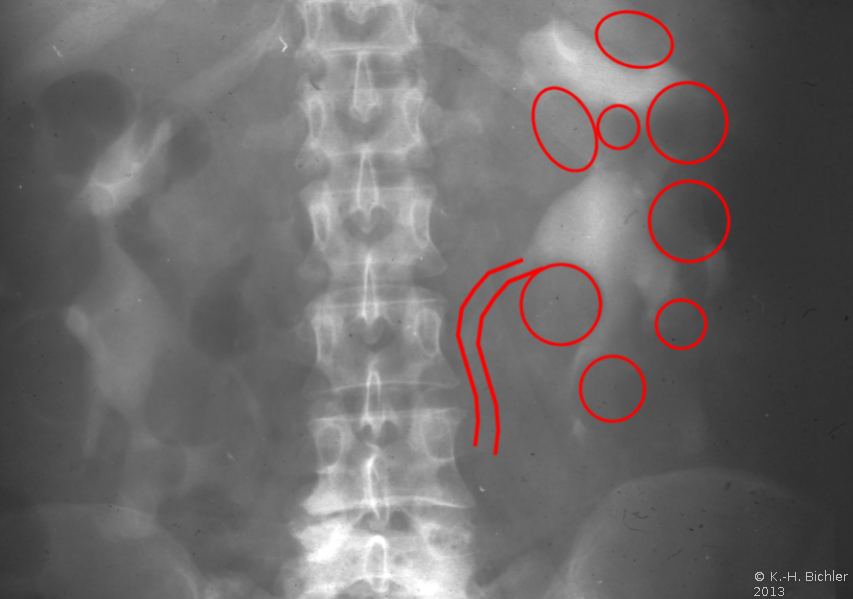

Ein i.v.-Pyelogramm kann im Rahmen der differentialdiagnostischen Abklärung des Flankenschmerzes indiziert sein (Abbildung). Sofern schon eine ausgeprägte Niereninsuffizienz vorliegt, sollte die Abklärung mit einem retrograden Pyelogramm erfolgen (Abbildung 5).